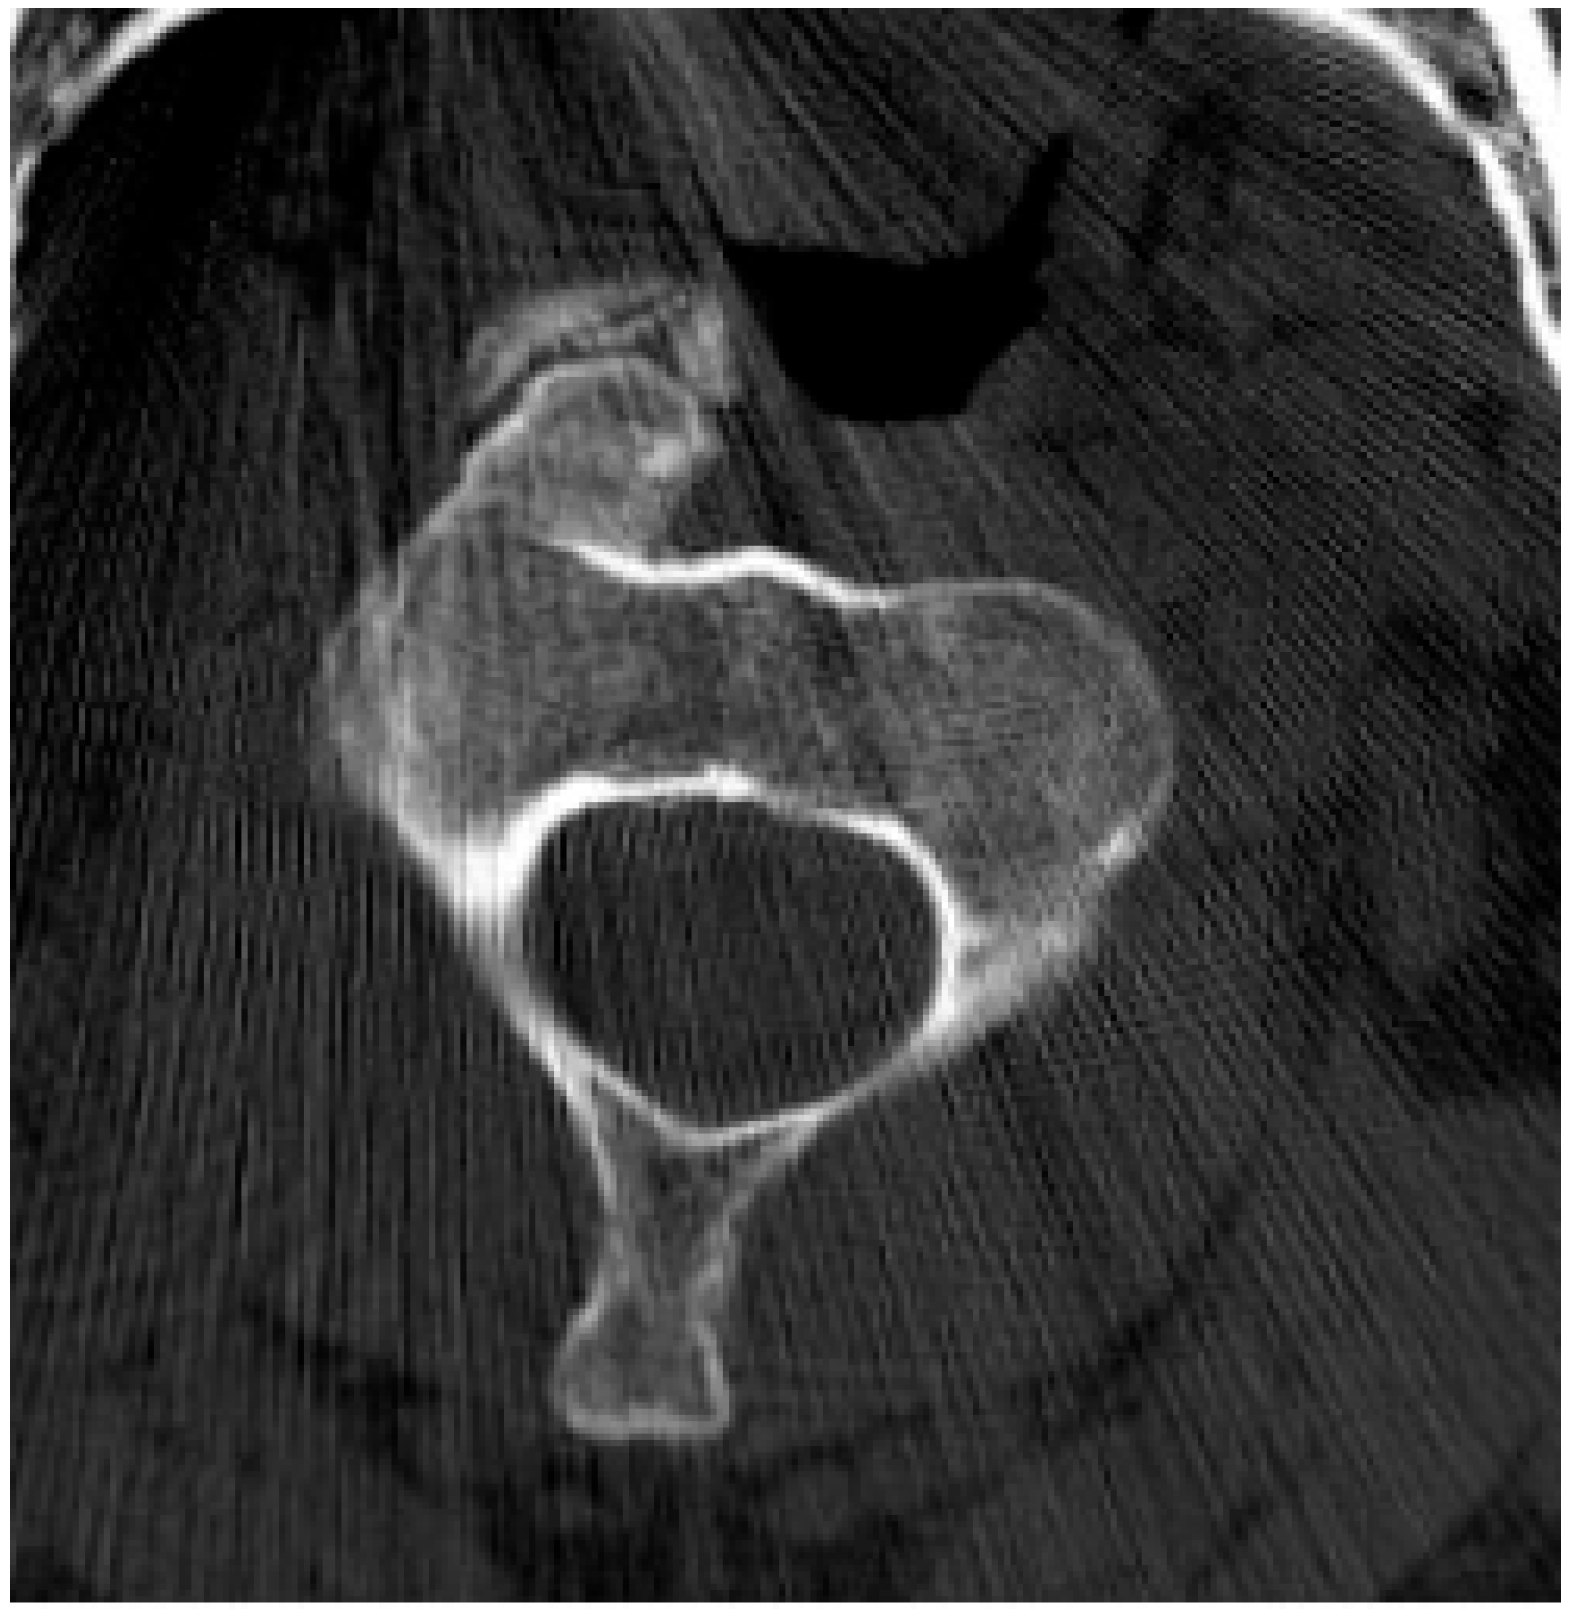

2.5.2. Aneurysmal Bone Cyst